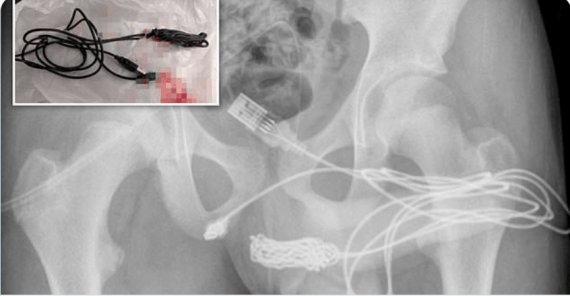

Ένας 15χρονος είχε την ιδέα να βάλει στο πέος του ένα… καλώδιο USB και το αποτέλεσμα ήταν να οδηγηθεί στο νοσοκομείο, όπου υποβλήθηκε σε χειρουργική επέμβαση.

Ο έφηβος από το Λονδίνο είπε στους γιατρούς ότι όλο αυτό έγινε γιατί «ήθελε να μετρήσει το μήκος του πέους του». Το «πείραμά» του όμως δεν πήγε καθόλου καλά και το καλώδιο σφήνωσε στο μόριό του, όπως αναφέρει σε δημοσίευμά της η Daily Mail.

Το αγόρι έκανε αρκετές προσπάθειες να αφαιρέσει μόνο του το καλώδιο, με αποτέλεσμα να αιμορραγήσει. Έτσι η οικογένειά του αναγκάστηκε να τον μεταφέρει στο νοσοκομείο.

Οι εργαζόμενοι στο νοσοκομείο δεν κατάφεραν επίσης να αφαιρέσουν το καλώδιο με τη χρήση ειδικών εργαλείων εξαιτίας της θέσης του, όπως ανέφεραν οι γιατροί στο Urology Case Reports. Το παιδί μεταφέρθηκε τότε εσπευσμένα στο University College Hospital του Λονδίνου.

Μετά από μια ακτινογραφία που αποκάλυψε το μέγεθος και τη θέση του, ο έφηβος μπήκε στο χειρουργείο. Τελικά, ύστερα από μια δύσκολη προσπάθεια, αφαιρέθηκε.